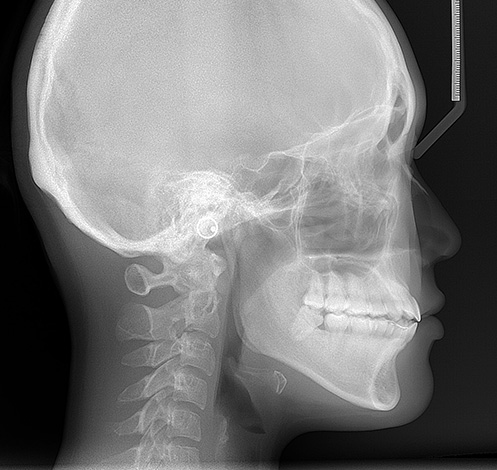

Dos métodos diagnósticos adicionais, os exames radiológicos são obrigatórios:

- O roentgenogram. Permite avaliar o crânio do paciente como um todo e ver quais fragmentos dos maxilares são mais curtos que outros;